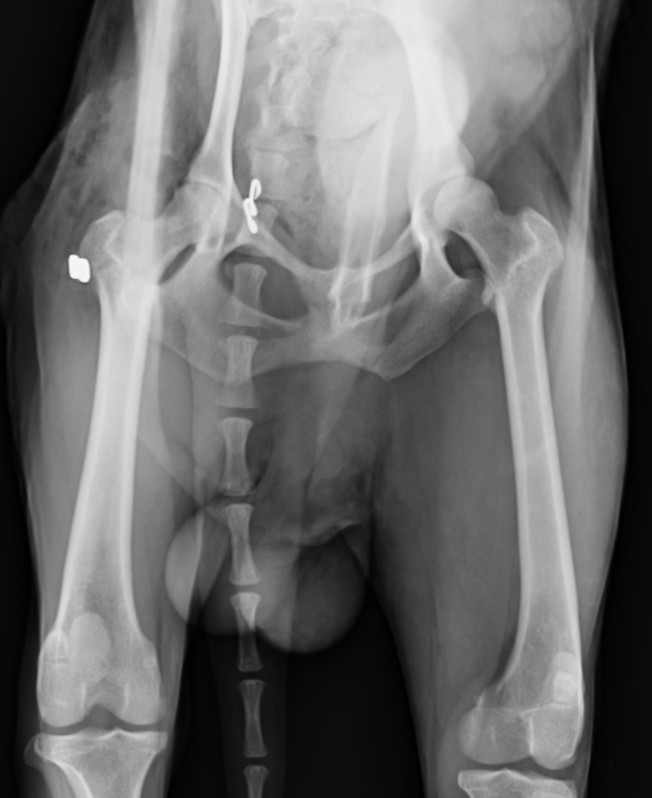

股関節脱臼

股関節とは骨盤の寛骨臼と呼ばれる凹みの部分に、大腿骨の大腿骨頭と呼ばれる球状の骨がはまることで関節しています。それが外傷や、寛骨臼の形成不全などによって抜けてしまうことを股関節脱臼といいます。

股関節が脱臼すると強い疼痛を引き起こし、足を地面に着けることができなくなり挙上してしまいます。股関節脱臼は脱臼する向きによって大きく2つに分けられます。90%が頭背側脱臼というもので、前方かつ、上方に脱臼してしまうタイプです。残りの10%が尾腹側脱臼というもので後方かつ、下方に脱臼してしまうタイプです。治療には用手による整復と、手術による治療がありますが、用手による整復の成功率は非常に低いとされており、基本的に手術によって整復します。頭背側脱臼ではワッシャーによる固定またはトグルピン法、骨頭切除などの術式が選択できます。症例によって治療法を選択しますが、可能であれば骨頭を切除せずに戻すのが理想と言えます。骨頭を切除すると術後の機能回復に時間がかかるのと、機能が元のの70〜80%にとどまると言われているからです。